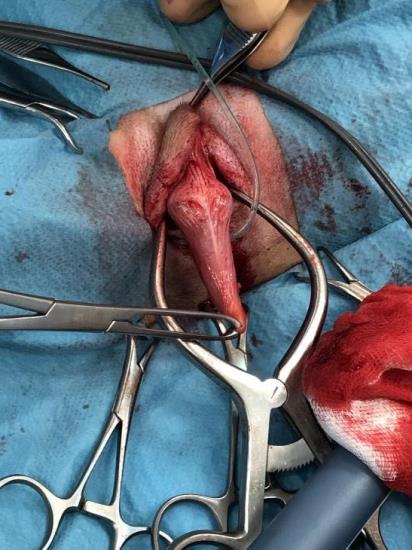

Delilah is a 7-month-old spaniel who was generally fit and well but had a recent history of worsening perivulval irritation. Although initial vulval examination had been unremarkable, a smooth, rounded structure, had recently been noted protruding from the vulva (Fig 1 & 2).

Although this structure was clearly abnormal, it was not possible to determine what it was from external examination alone. The two main differential diagnoses were either clitoral hypertrophy or a pseudophallus secondary to an intersex condition. These two conditions can be distinguished by determining the site of the urethral orifice. The urethra should open separate from the clitoris and so clitoral hypertrophy would be considered likely if these two structures were separate. If, however, the urethral orifice was associated with the structure then a pseudophallus condition would be considered more likely. In Delilah’s case, the urethral orifice was sited at the dorsal aspect of the structure and so a diagnosis of intersex was made. An abdominal ultrasound examination was performed and two, intra-abdominal gonads were identified.

Delilah was then anaesthetised and taken to surgery. The urethra was identified and catheterised (Fig 3) and an episiotomy performed to give safe access to the urethral orifice. The pseudophallus was then gradually dissected free from its attachments (Fig 4) and a mucosal flap containing the urethral orifice was raised and separated from the phallus using a harmonic scalpel (Fig 5). The phallus was then amputated and the mucosal flap and urethra were then sutured into the mucosal defect left from phallus removal (Fig 6).